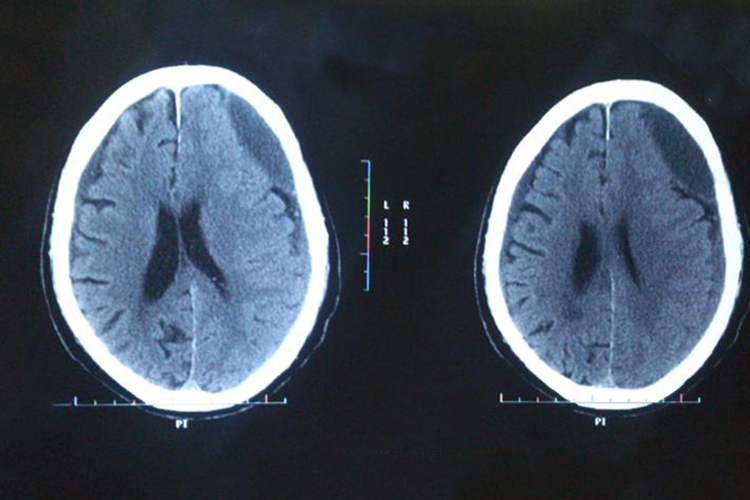

左侧硬膜下血肿是因血液淤积在左侧硬脑膜下腔形成的多发性血肿,CT可见高密度影像或点状出血灶,还可伴有头晕、呕吐等症状。

左侧急性硬膜下血肿CT检查示颅骨内板与脑组织表面之间有高密度、等密度或混合密度的新月形或半月形影;慢性硬膜下血肿CT检查示颅骨内板下低密度的新月形、半月形或双凸镜形影,还可出现中线移位、脑室受压的情况。